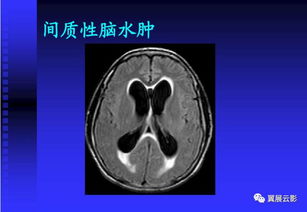

MRI已成為癲癇診斷和處理的主要工具。MRI對哪怕只有很少量水分的增加都可以敏感的發(fā)現(xiàn),且具有骨偽影少的特 點,能更精確地顯示某些癲癇病人CT掃描不能發(fā)現(xiàn)的腦結(jié)構(gòu)改變,如無癥狀的神 經(jīng)膠質(zhì)瘤、胚胎發(fā)育不良神經(jīng)上皮瘤、海綿狀血管瘤、腦梗死、腦出血后及外傷 后腦損傷灶、局灶性腦萎縮和腦穿通畸形等。